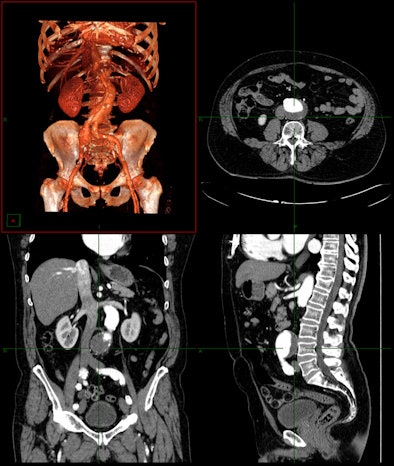

![]() |

| Enterprise-wide 3D can deliver value in a wide variety of clinical situations. Image courtesy of Carestream Health. |